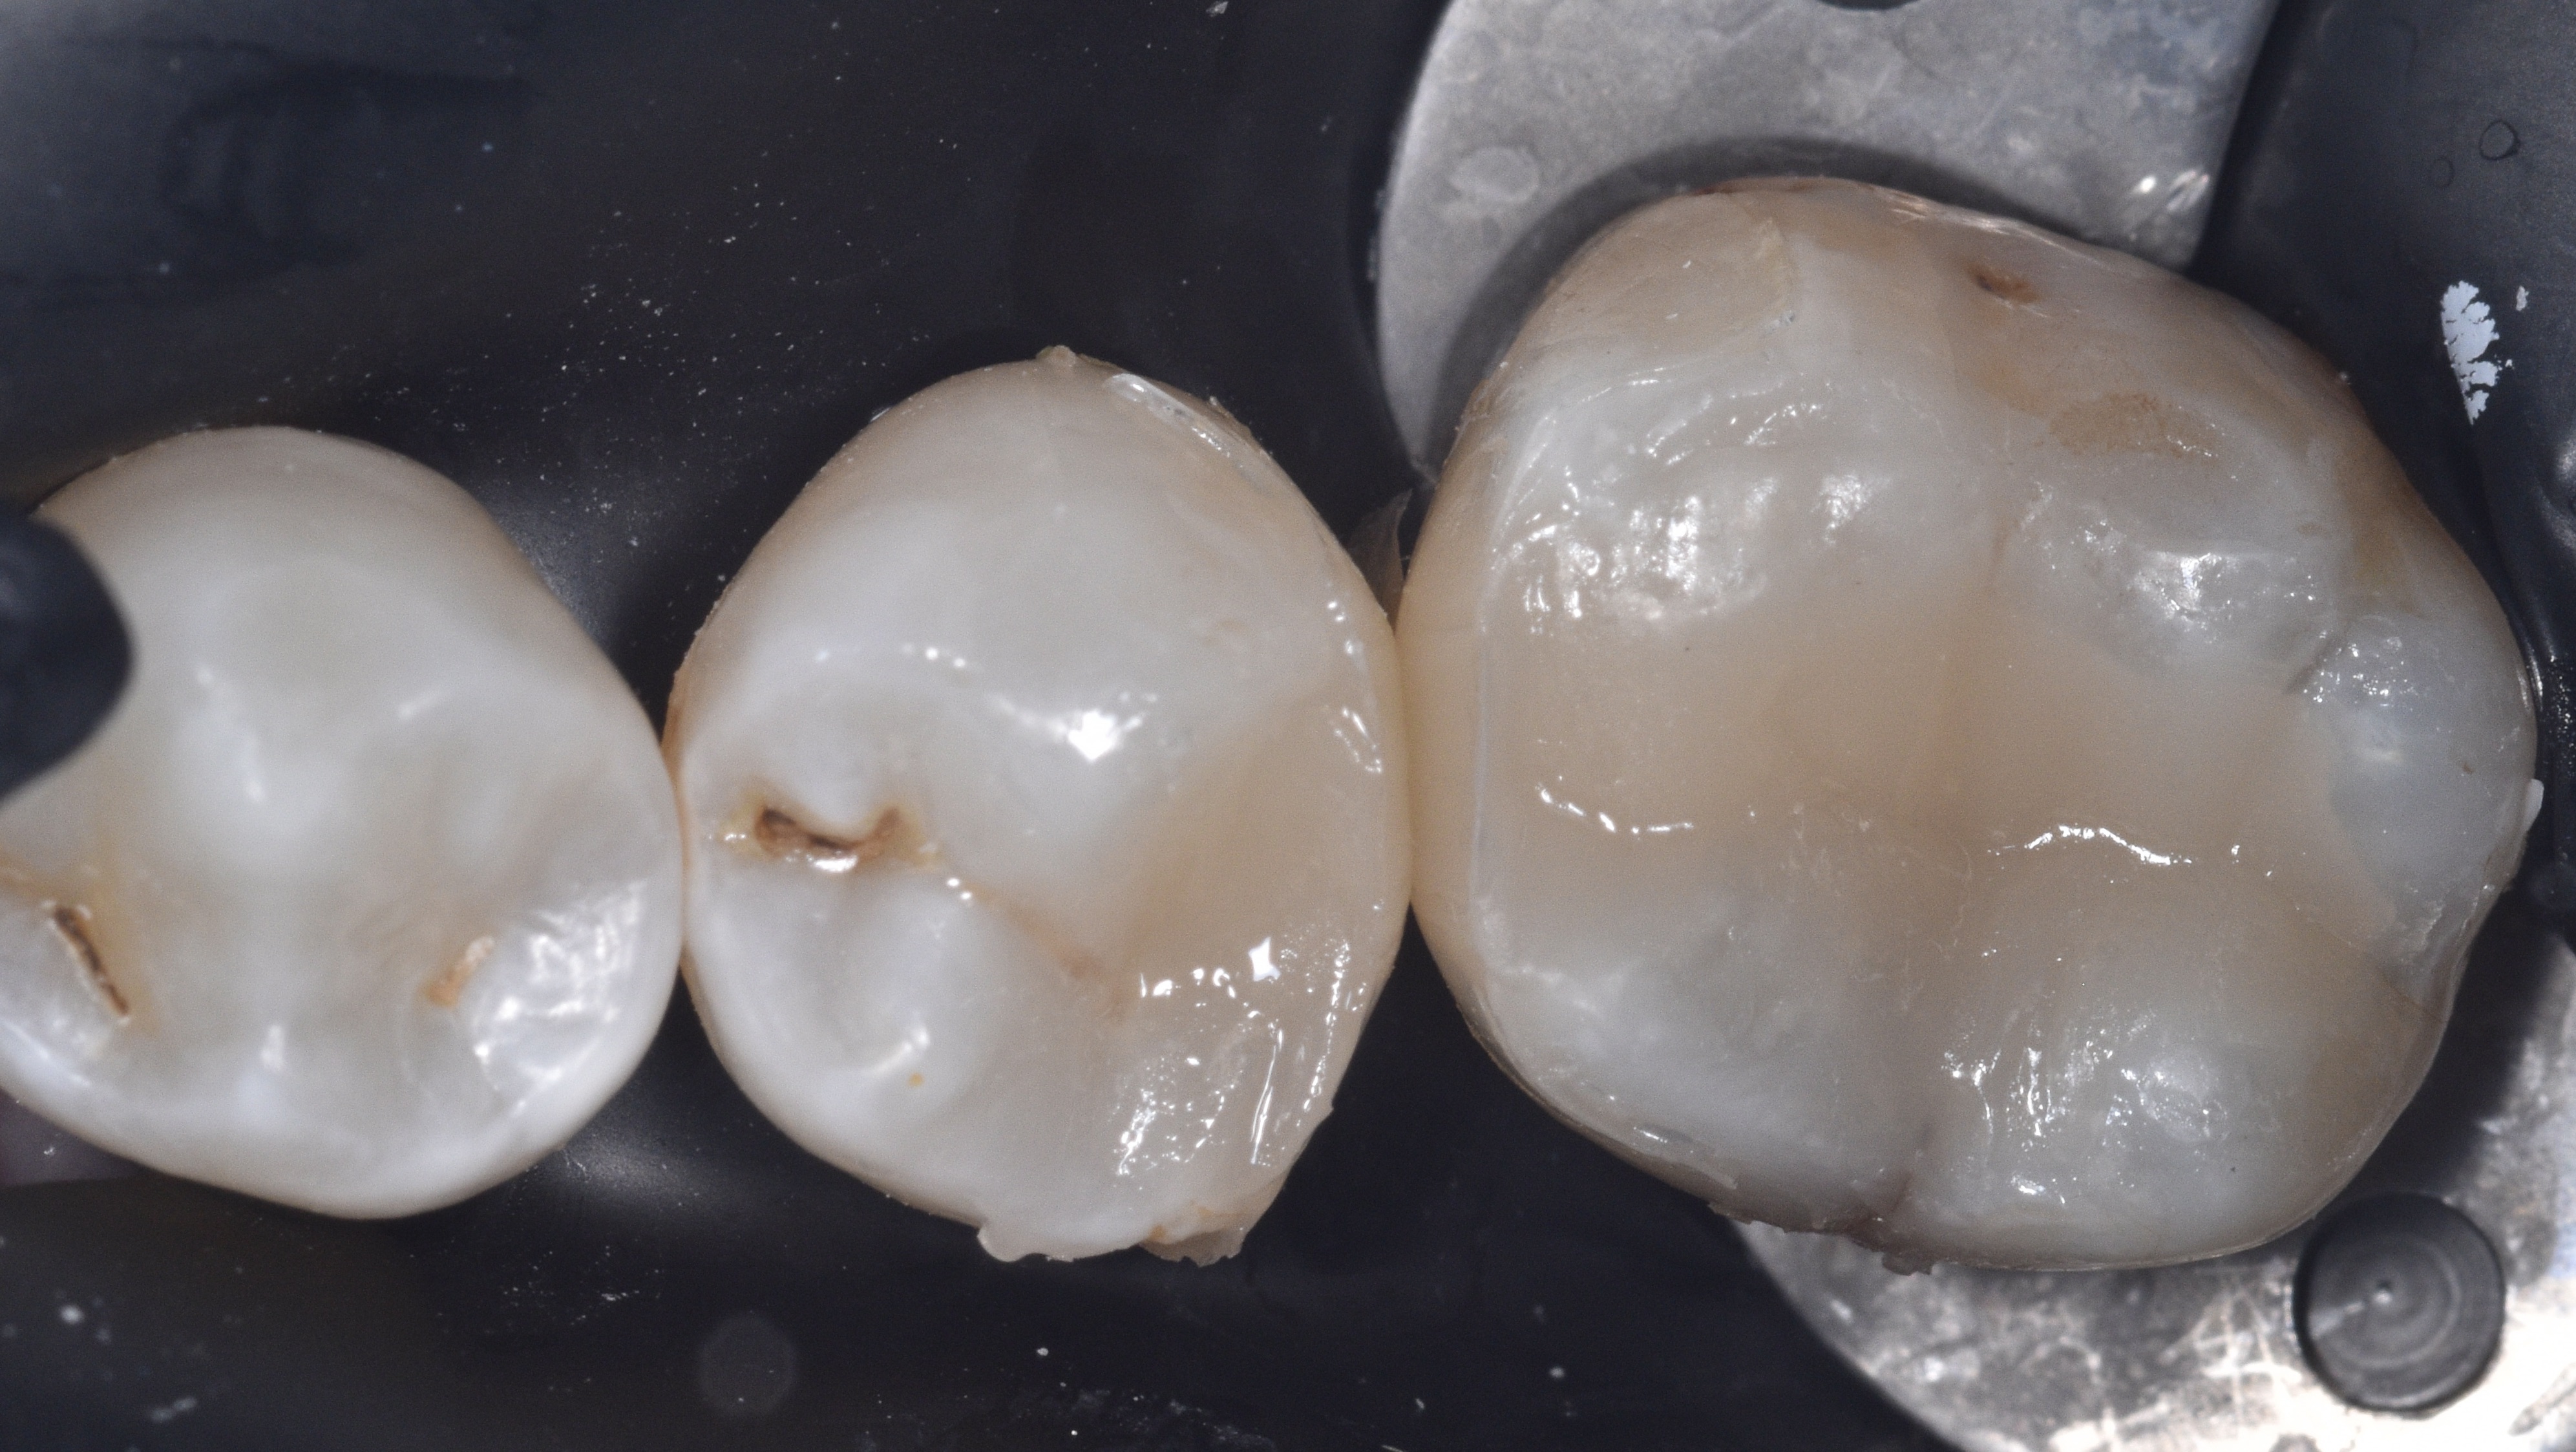

Following caries removal, the walls of the cavity preparations were beveled using a fine diamond mosquito bur, as shown in Figure 3. The prepared surfaces were then air abraded with 23-micron aluminum oxide particles combined with distilled water, using the AquaCare system, to further clean and prepare the tooth structure for restoration.

Figure 3. Walls of cavity preparations were beveled using a fine diamond mosquito bur. Figures 4-5. Quad wedge and ring system used for this case.